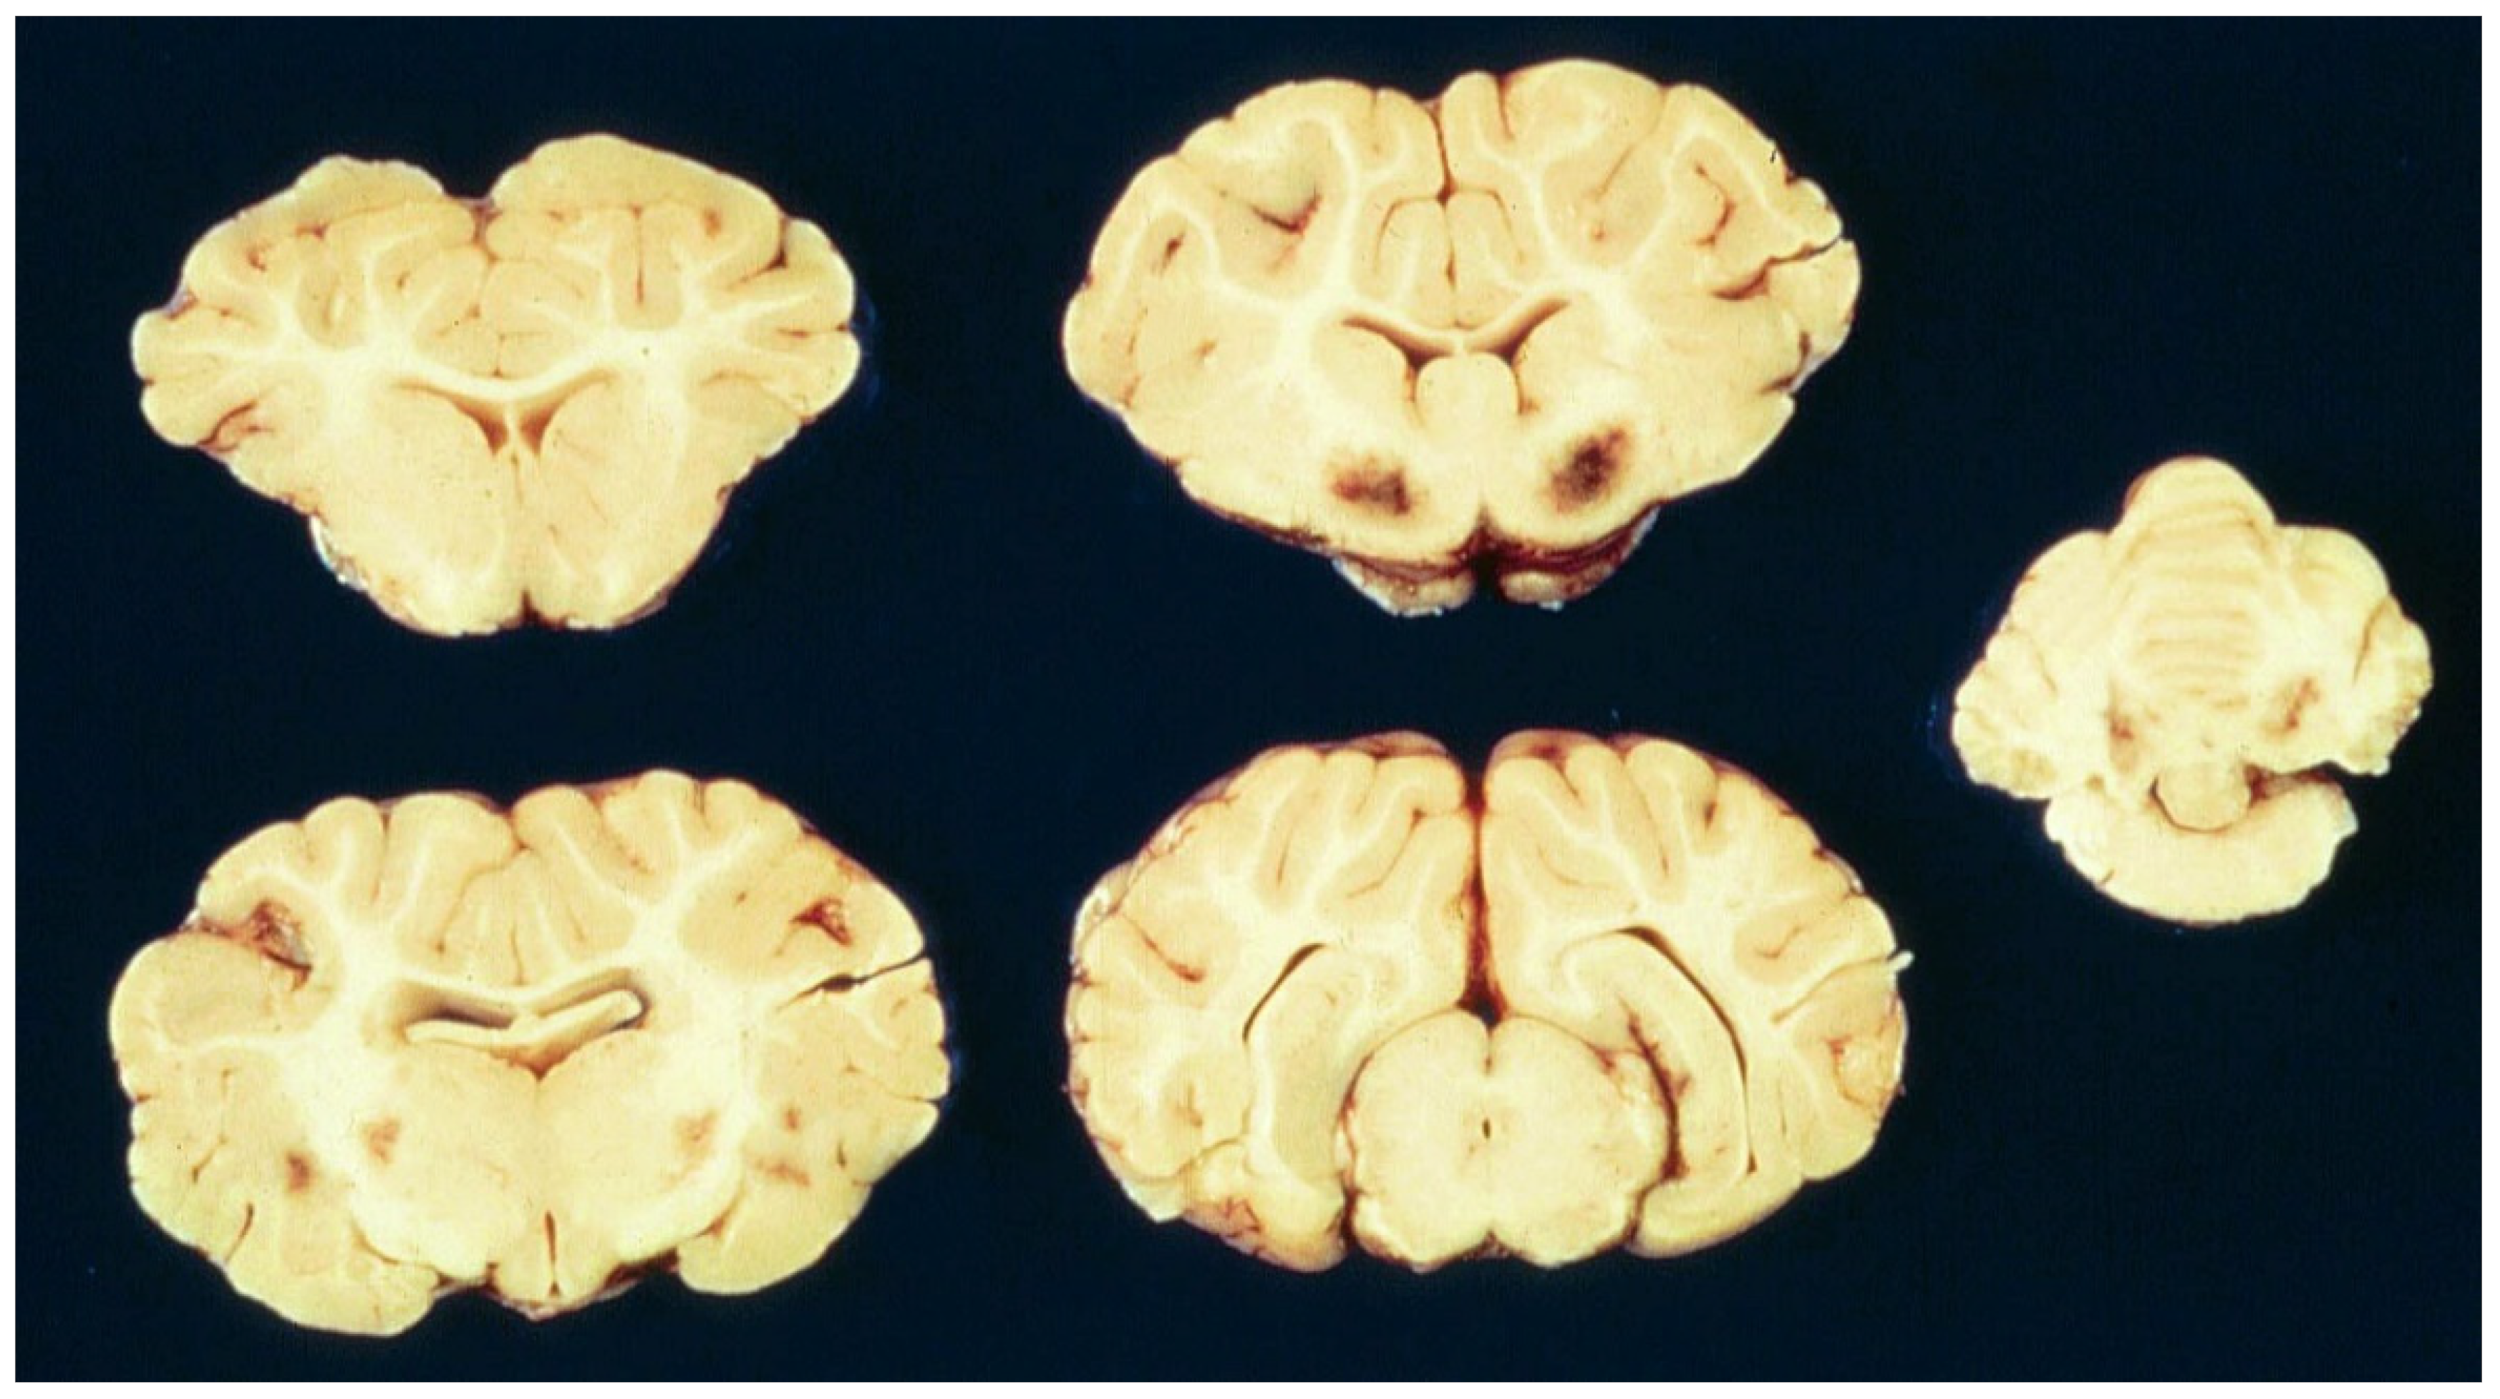

6.2. Neuropathology